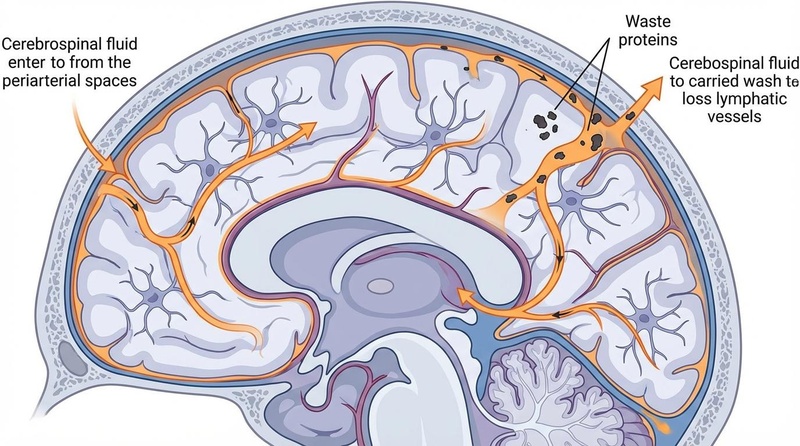

Sleep is the critical period for neurotoxin clearance and synaptic homeostasis, directly fueling the brain's ability to focus and process information. Rather than merely avoiding fatigue, high-quality sleep actively restores the neural networks required for vigilance.

| Sleep & Exercise | Glymphatic clearance, BDNF | Foundation of cognition | 🟢 Validated |